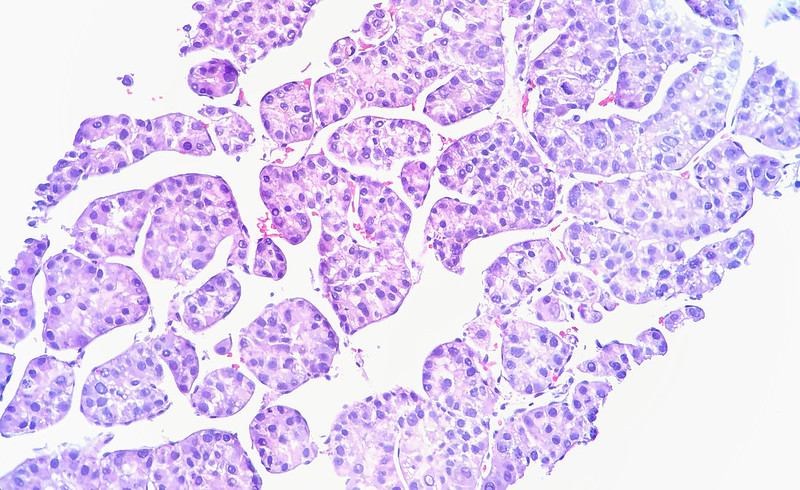

Image by Flickr user Ed Uthman via a Creative Commons license